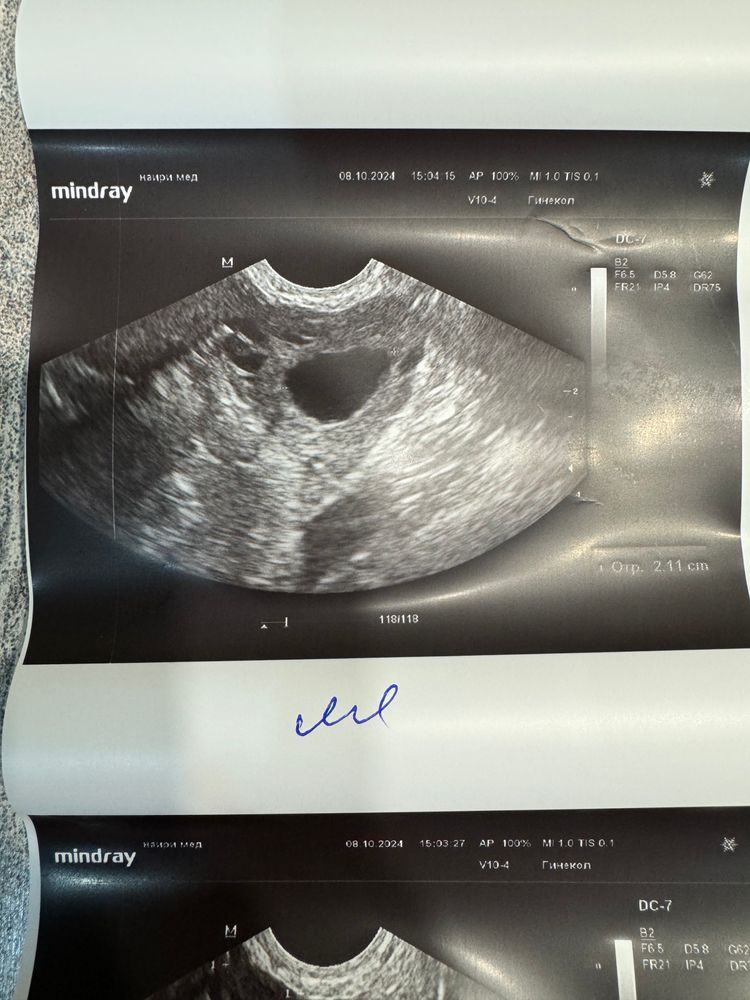

Снова разглядываю свое узи. Фолликул такой странной формы уже. 19 дц, слева 21 мм. Говорили вчера, что «овуляция сегодня-завтра». Смущают такие края неровные.. может овуляция после узи была? Или сегодня? Как думаете? Пик лг на тестах не поймала.. но я его никогда не ловила, даже когда было уже жт.

Повторно только в пятницу гляну как там..